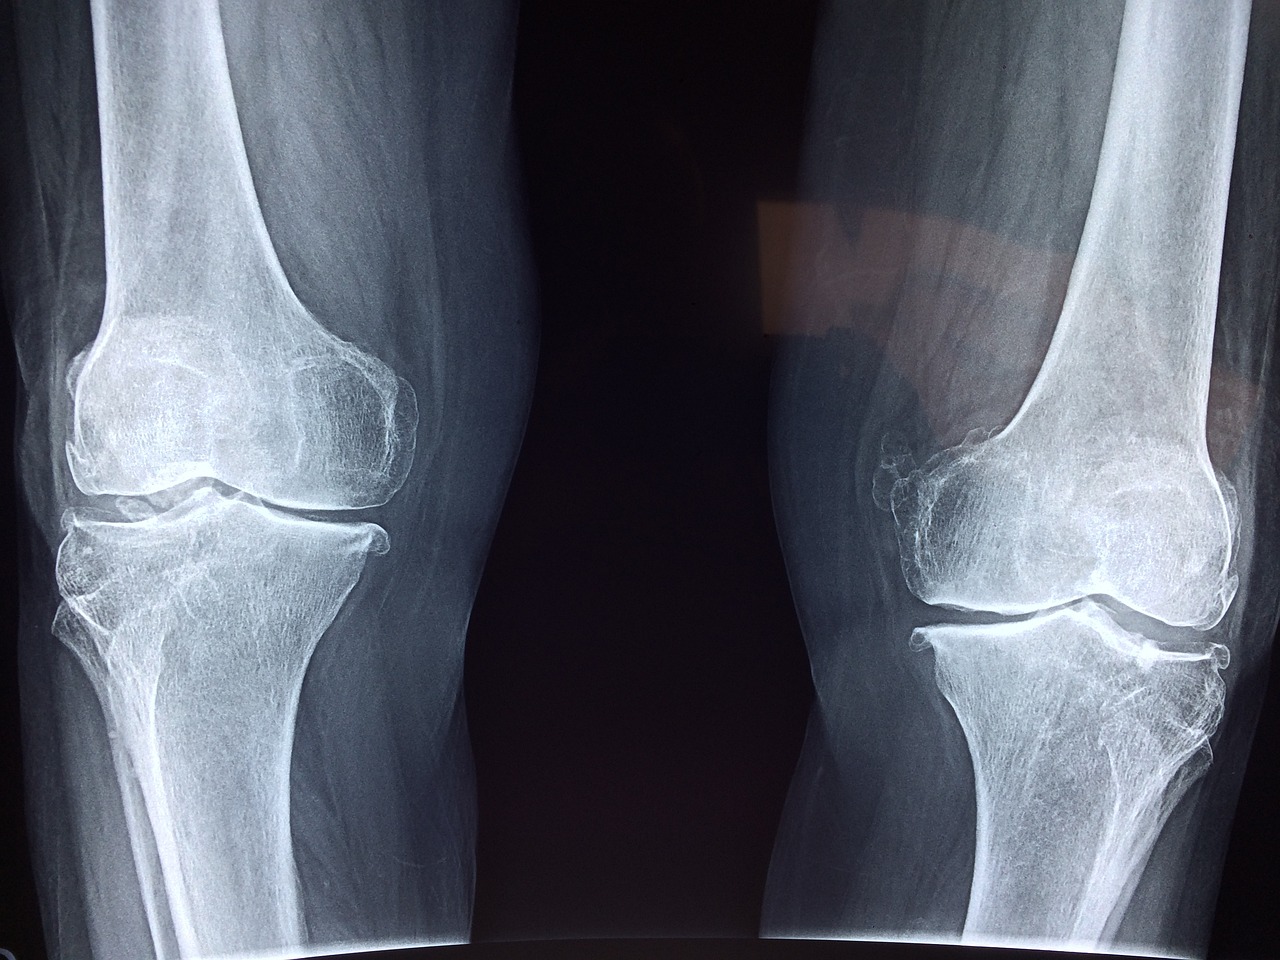

무릎 연골 손상시 치료방법

검진을 통해 무릎 연골이 손상된 것을 확인했다면 보존적 치료인 ✅약물 치료 ✅주사 치료 ✅ 물리 치료 등으로 치료하지만 이보다 심할 경우에는 수술이 불가피할 수도 있습니다.

관절 내시경 수술을 통해 절개 후 내시경과 수술 기구를 통해 직접 무릎을 확인하면서 시행하는 수술을 진행할 수도 있는데요 이럴 경우 3~5일가량 회복 기간이 필요합니다.